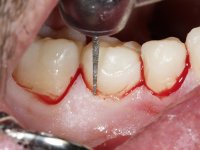

Realizado o diagnóstico e tomada a decisão quanto ao tratamento a executar, tornou-se importante definir qual a sequência de trabalho a adotar no sentido de conseguir a reabilitação da D.V.O. (V.D.O), de forma progressiva e equilibrada. Na primeira fase fez-se uma pré-impressão da arcada inferior com silicone tipo “putty” e em seguida realizou-se o preparo dentário de todo o sector posterior. O preparo para os overlays foi feito coronalmente à linha amelo cementaria no sentido de ser o mais conservador possível. A impressão foi feita com técnica de dupla mistura após afastamento gengival realizado com pasta de caulino. A provisória foi realizada com resina composta de polimerização dual. Em laboratório foram realizados os overlays após se ter aberto ligeiramente (1,5mm) a D.V.O. nos modelos montados em articulador semi-ajustável. Simultaneamente o sector antero-inferior foi encerado no sentido de acompanhar este aumento da D.V.O. Também foi confecionada uma chave de silicone translucido para posterior confeção dos provisórios antero-inferiores. Em boca foi primeiro realizada a provisionalização dos dentes anteriores utilizando resina composta previamente aquecida após preparação das superfícies dentárias para a adesão. Foi colocado o dique de borracha para promover o isolamento absoluto e posteriormente foram colados os overlays. Em laboratório foi realizada nova chave de silicone para confecionar os provisórios antero-superiores. Seguidamente em boca foram preparados os seis dentes antero-superiores após colocação do fio de afastamento gengival. Feita a preparação adequada das superfícies dentárias foi realizada a impressão com técnica de dupla mistura e a respetiva provisória. Em laboratório foram confecionadas 6 facetas feldespáticas num modelo de trabalho tipo “Geller”. A provisória foi removida e as facetas foram coladas em boca utilizando um isolamento relativo competente. Esta opção foi tomada em virtude de uma prévia experiencia negativa com a colocação do dique de borracha na mandibula. Após a colagem dos laminados antero-superiores foram dadas 12 semanas para avaliar a adaptação do paciente à nova situação e então iniciar a confeção das facetas antero-inferiores. Após colocação do fio de afastamento gengival. foram feitos os preparos dentários adequados e em seguida foi feita a impressão. Também foi feita a preparação do dente 3.4 que, entretanto, tinha sofrido uma fratura do overlay. As facetas e a restauração do 3.4 foram realizadas num modelo de trabalho tipo “Geller”. Após remoção da provisória, as facetas foram coladas em boca, utilizando um isolamento relativo pelas razões apontadas anteriormente. Após colocação do trabalho o paciente foi reabilitado por outros colegas com um implante na zona do 2.6 e substituição da coroa aparafusada sobre o implante colocado no local do 3.5. Posteriormente surgiram fraturas nos overlays dos dentes 4.7 e 3.7 que foram reabilitados com overlays em Zr.